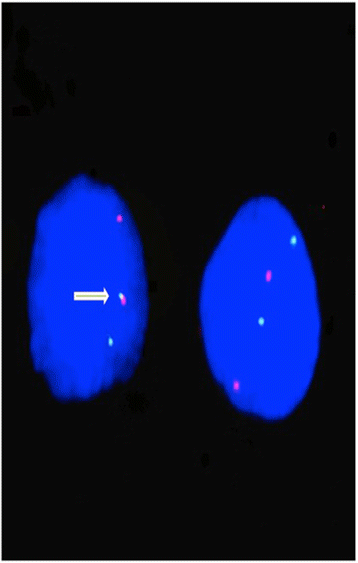

Methods: Total DNA was extracted from paraffin-embedded tissues from 45 biopsies of oncocytic tumors. High-resolution melting was used for mutation screening of mitochondrial complex I subunits genes. Specific nuclear rearrangements were investigated by RT-PCR (RET/PTC) or on isolated nuclei by interphase FISH (PAX8/PPARγ). Recurrent point mutations were analyzed by direct sequencing.